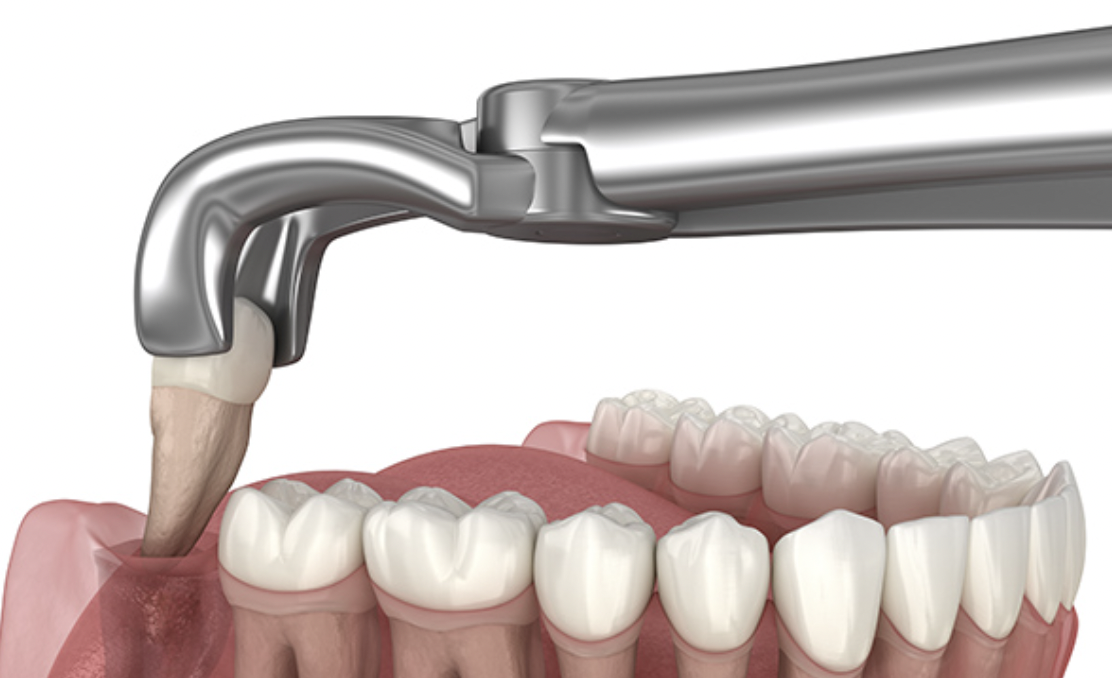

고난도의 매복된 사랑니 발치

사랑니가 매복되어 있거나 턱뼈 안쪽에 깊숙이 위치한 경우,

고난도의 시술이 필요할 수 있습니다. 매복된 사랑니나 복잡한

사랑니 위치에도 안전하고 정확한 수술을 제공하여

환자들의 안전을 최우선으로 합니다.

사랑니가 매복되어 있거나 턱뼈 안쪽에 깊숙이

위치한 경우,고난도의 시술이 필요할 수 있습니다.

매복된 사랑니나 복잡한 사랑니 위치에도 안전하고

정확한 수술을 제공하여 환자들의 안전을

최우선으로 합니다.